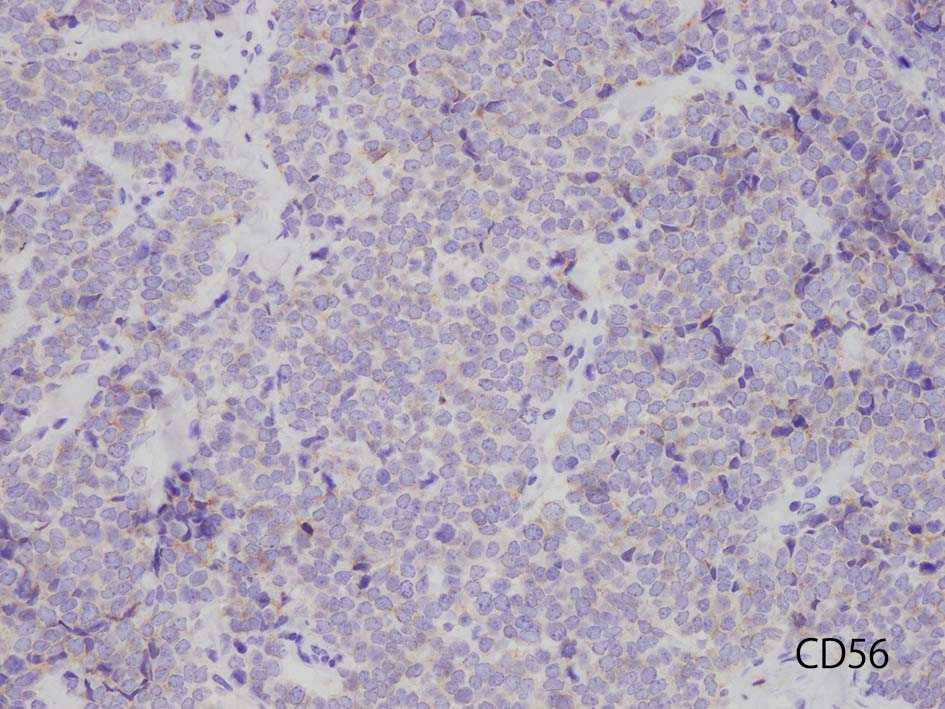

- 陽性神経内分泌マーカ; chromograninA, synaptophysin, CD56, NES

免疫染色

CD56

本例ではCD56は淡くそまるのみであった. 浜松医大病院病理で染色していただいた, MCpvVは核に陽性となっている.